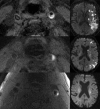

Carotid therosclerotic disease causes approximately 25% of the nearly 690,000 ischemic strokes each year in the United States. Current risk stratification based on percent stenosis does not provide specific information on the actual risk of stroke for most individuals. Prospective randomized studies have found only 10 to 12% of asymptomatic patients will have a symptomatic stroke within 5 years. Measurements of percent stenosis do not determine plaque stability or composition. Reports have concluded that cerebral ischemic events associated with carotid plaque are intimately associated with plaque instability. Analysis of retrospective studies has found that plaque composition is important in risk stratification. Only MRI has the ability to identify and measure the detailed components and morphology of carotid plaque and provides more detailed information than other currently available techniques. MRI can accurately detect carotid hemorrhage, and MRI identified carotid hemorrhage correlates with acute stroke.